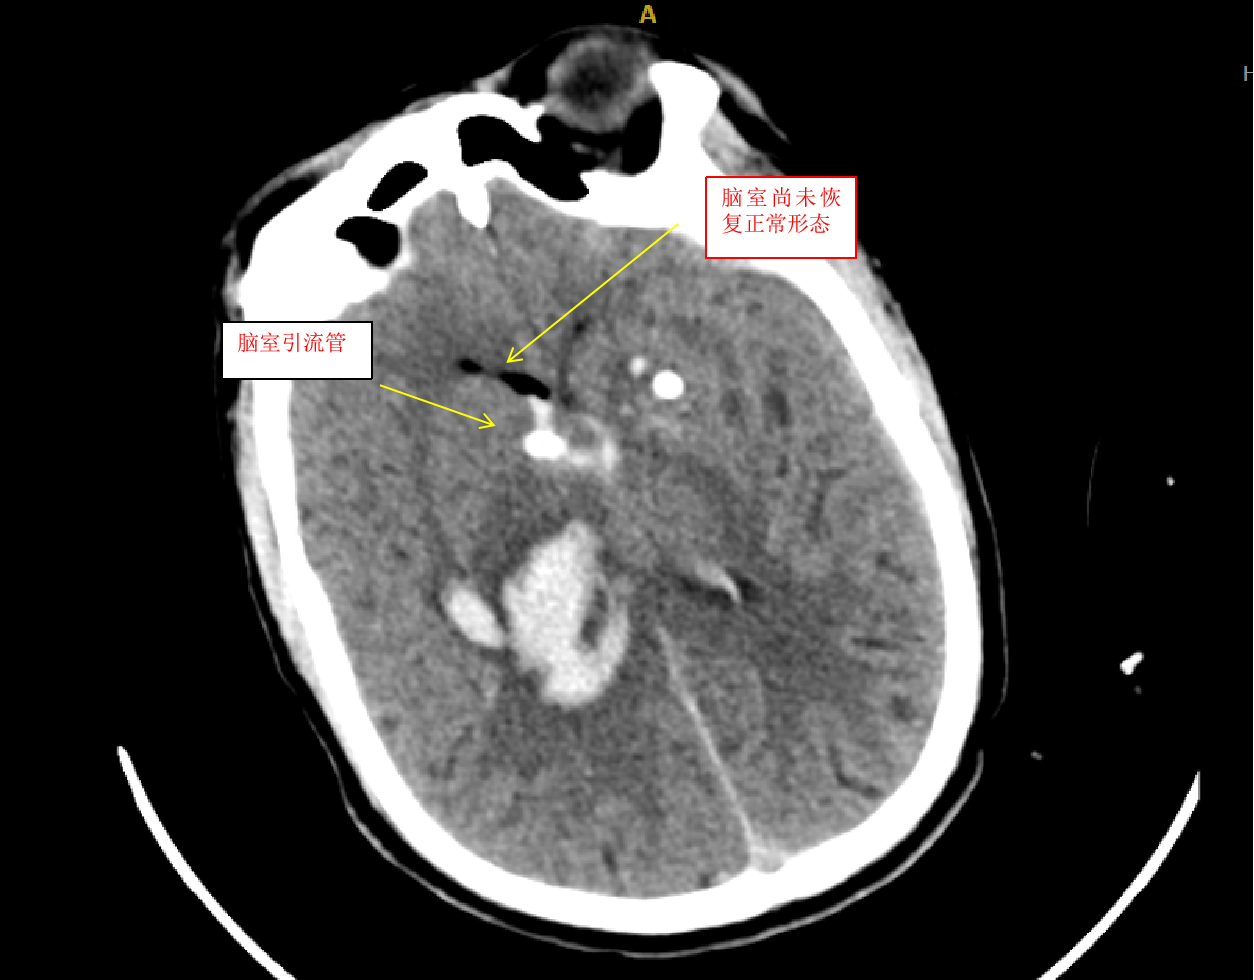

我们收到此病人后,立即给予术前准备,并在局麻下行双侧脑室外引流术,由于病人脑室有大量出血,穿刺置管有很大的技巧,因为大量的脑室出血,致脑室铸型,打乱了正常的解剖结构,穿刺失败的可能性很大。经术后复查颅脑CT,发现右侧管道引流较通畅,决定拔除左侧引流管,并通过右侧引流管给予尿激酶注入反复溶解血块并引流出血性液体,共应用尿激酶10次,每日一次,为了预防感染,并在每次冲洗时给予严格换药。于第10天经复查颅脑CT发现脑室出血已基本清除,决定给予拔除脑室引流管。为了放出残留血性脑脊液,尽量廓清病人脑脊液,于拔管后第二天开始给予腰穿,共进行腰穿10次,每日一次,腰穿时尽量多放出脑脊液,才能取得更好的效果。于近日复查颅脑CT发现丘脑出血已完全吸收,脑室积血已完全清除,未出现脑积水,未出现颅内感染。经过这段时间的治疗后病人的意识状况已明显好转,由深昏迷转为神志恍惚,肢体的偏瘫也逐渐好转,目前仍给予肢体康复训练治疗,几天后就能治愈出院。